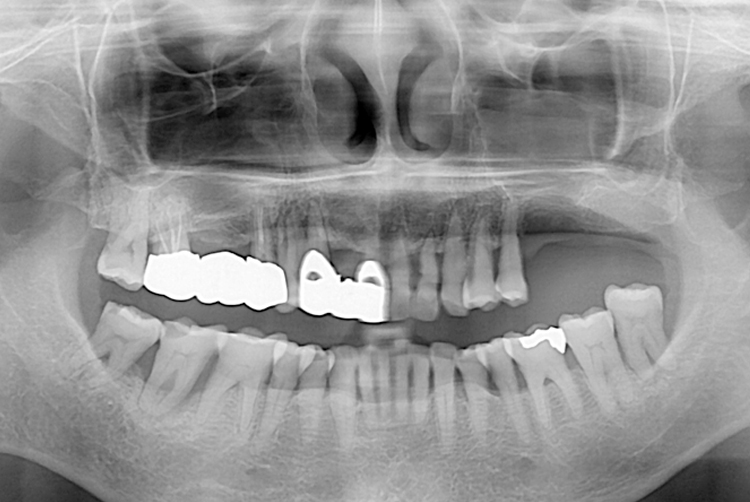

22.03.29.jpg

치료후 : 2022-03-29

세종치과는 많은 환자와 다양한 케이스를 바탕으로 항상 편안한 임플란트 수술을 제공하고자 노력하고,

오래동안 튼튼히 쓸 수 있는 임플란트 수술을 가장 큰 목표로 삼고 있습니다